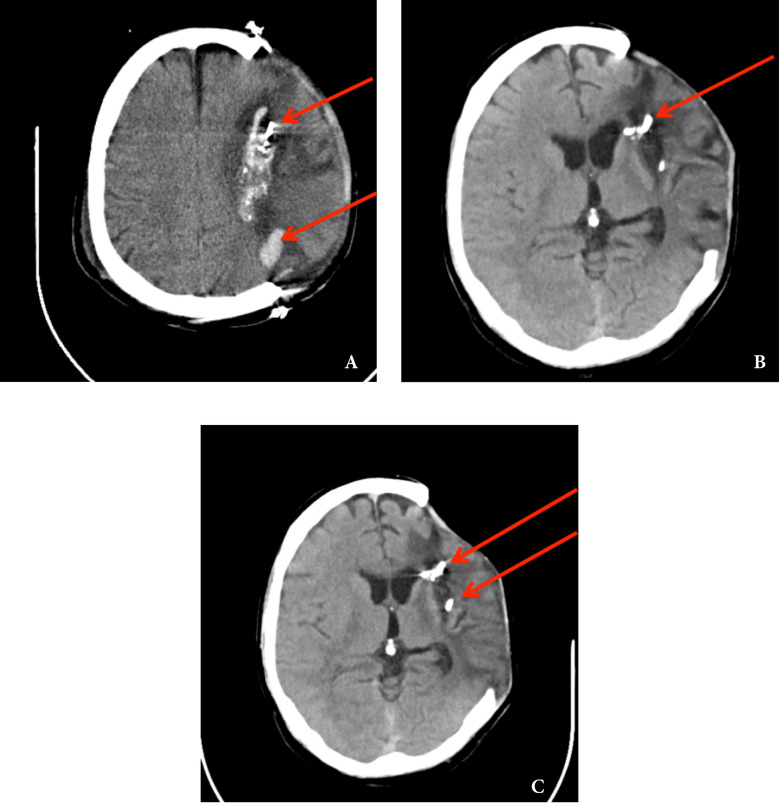

术后早期非对比头部CT扫描显示左半球弥漫性水肿,肿块突出于颅骨缺损的边缘,穿透性伤口冲击通道中充满残留的异物和脑出血(图6 a)。

图6、术后早期颅脑自然轴位CT扫描显示左半球弥漫性水肿,肿块突出于颅骨缺损的边缘,穿透性伤口撞击路径充满残留异物,并出现颅内出血(箭头)(a)。在损伤后第45天进行的复查自然轴位脑CT显示轴位内脑出血几乎完全消退,伴有零星的创伤后脑病区和残留的骨碎片(箭头),但没有肿块效应/中线移位,左侧脑室前角轻微增大(b)。在6个月的检查中执行的大脑对照轴位CT显示左额顶叶区创伤后脑实质缺失区域以及右额顶叶中残留的异物(箭头)(c)

在损伤后第45天进行的复查自然轴位脑CT证实了轴位内出血几乎完全消退,伴有零星的创伤后脑病区和残留的骨碎片,但没有压迫性肿块效应/中线移位和左侧脑室前角的轻微脑室扩大(图6 b)。在6个月的检查中进行的大脑的对照天然轴位CT显示了左额顶区的创伤后脑实质损失区(图6 c)。